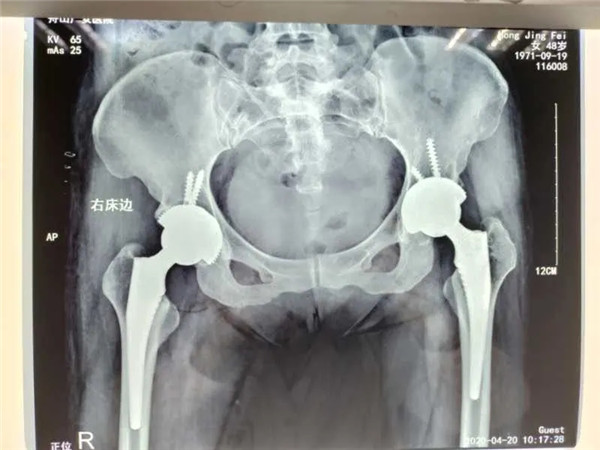

4月13日,危立軍副院長為洪女士實施了右側髖關節(jié)置換術,手術在關節(jié)鏡下完成,術后洪女士感覺良好。術后一周,洪女士便可以下地行走。目前,洪女士恢復良好,已經出院回家休養(yǎng)。

雙側髖關節(jié)置換

值得一提的是,對于此次手術的人工關節(jié)材料,洪女士仍舊和三年前一樣,選擇了全陶瓷人工關節(jié)。

據危立軍副院長介紹,金屬、陶瓷和聚乙烯是目前人工關節(jié)假體的主要制作材料。而相對于另外兩種,全陶瓷人工關節(jié)假體的硬度最大、最耐磨。陶瓷的特點是硬度大,超耐磨,有一定的脆性。很多股骨頭壞死的病人都存在一個誤區(qū),就是擔心人工關節(jié)使用壽命不高(以前的高分子容易磨損,平均使用壽命15年),對于病癥能拖盡可能拖,往往等到疼痛難忍了才選擇開刀做手術,錯失了最合適的手術時間,大大降低了生活質量。隨著第四代陶瓷關節(jié)的出世,使用壽命可達50年,是股骨頭壞死患者的福音。